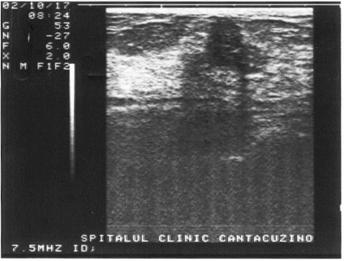

INTARIREA ACUSTICA

Peretele ce

separa o structura lichidiana de o structura solida constituie o interfata.

Deoarece diferenta de densitate dintre cele doua structuri este mare, interfata

este foarte evidenta; la acest nivel producandu-se o reflectare masiva de

ecouri. Interfata ce separa mediul solid de cel lichidian devine astfel foarte

ecogena. Aceasta ecogenitate se propaga pe distante mici, distal de structura

lichidiana in mediul urmator. Cu cat aceasta propagare distala a ecogenitatii

interfetei este mai mare, cu atat este mai mare diferenta de densitate dintre

mediul strabatut (lichidian) si cel ce urmeaza (solid).

Figura 16. Intarire acustica posterioara la nivelul vezicii urinare.

Figura 17.}ntarire acustica posterioara la nivelul V.B.